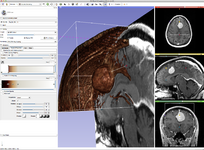

- Slicer 4.0 includes a major overhaul of the user interface, improved and simplified workflows for major tasks, simplified procedures for developers, and improved Python support.

Slicer is a community platform created for the purpose of subject specific image analysis and visualization.

- Multi-modality imaging including, MRI, CT, US, nuclear medicine, and microscopy

Slicer Highlights